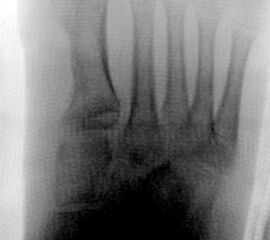

In der Regel bestehen aktive Wachstumsfugen bei Mädchen bis zum 12. und bei Jungen bis zum 14. Lebensjahr, mit Abweichungen von einem Jahr nach unten und nach oben. Präzise Informationen unter anderem darüber gibt das präoperative Röntgenbild (Abb. 2).

Abb. 2 a-c: offene Wachstumsfugen MT I Basis und Zehen (a), teilweise geöffnete Wachstumsfugen (b) und geschlossene Wachstumsfugen (c).

Die erforderlichen Osteotomien sind daher dem Fugenverlauf anzupassen, diese sind unbedingt zu respektieren. Wird eine Wachstumsfuge versehentlich mit der Fräse verletzt, kann durch partiellen oder kompletten Fugenverschluss ein Fehlwachstum provoziert werden. Achsabweichungen oder ein Wachstumstopp der betroffenen Region können die Folge sein. Offene Wachstumsfugen begrenzen die Osteotomieausrichtung besonders im Bereich des dorsalen Calcaneus, der Metatarsale I Basis und der IV. oder V. Zehe im End- und Mittelglied.